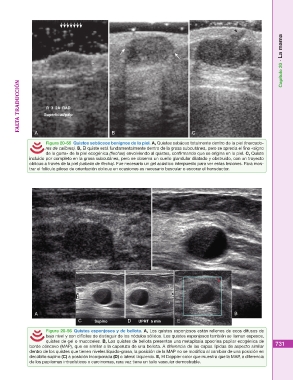

Figura 20-55 Quistes sebáceos benignos de la piel. A, Quistes sebáceo totalmente dentro de la piel (marcado-

res de calibres). B, El quiste está fundamentalmente dentro de la grasa subcutánea, pero se aprecia el fino «signo

de la garra» de la piel ecogénica (flechas) envolviendo al quistes, confirmando que se origina en la piel. C, Quiste

incluido por completo en la grasa subcutánea, pero se observa un cuello glandular dilatado y obstruido, con un trayecto

oblicuo a través de la piel (cabeza de flecha). Fue necesario un gel acústico interpuesto para ver estas lesiones. Para mos-

trar el folículo piloso de orientación oblicua en ocasiones es necesario bascular o escorar el transductor.

Figura 20-56 Quistes esponjosos y de bellota. A, Los quistes esponjosos están rellenos de ecos difusos de 731

bajo nivel y son difíciles de distinguir de los nódulos sólidos. Los quistes esponjosos también se llaman espesos,

quistes de gel o mucoceles. B, Los quistes de bellota presentan una metaplasia apocrina papilar ecogénica de

borde cóncavo (MAP), que es similar a la caperuza de una bellota. A diferencia de las capas lípidas de aspecto similar

dentro de los quistes que tienen niveles líquido-grasa, la posición de la MAP no se modifica al cambiar de una posición en

decúbito supino (C) a posición incorporada (D) o lateral izquierdo. E, El Doppler color que muestra que la MAP, a diferencia

de los papilomas intracísticos o carcinomas, rara vez tiene un tallo vascular demostrable.